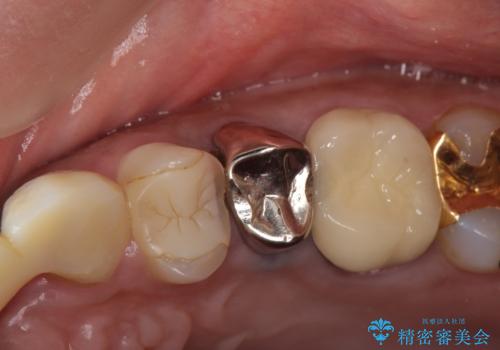

左上4、5番目の歯は根尖病変を認めたため再根管治療を行い、オールセラミッククラウンによる補綴を行いました。

なお左上4に関しては縁下歯質を改善するため、歯冠挺出を行っております。

今回用いたオールセラミッククラウンは、ジルコニアフレームという白い素材の上にセラミックを盛っているため審美性が非常に高いのが特徴です。

またジルコニアは人工ダイヤモンドの材料にも使われているほど高い強度を持っており、そのためオールセラミッククラウンは審美性だけでなく、奥歯やブリッジの補綴も可能とするクラウンです。